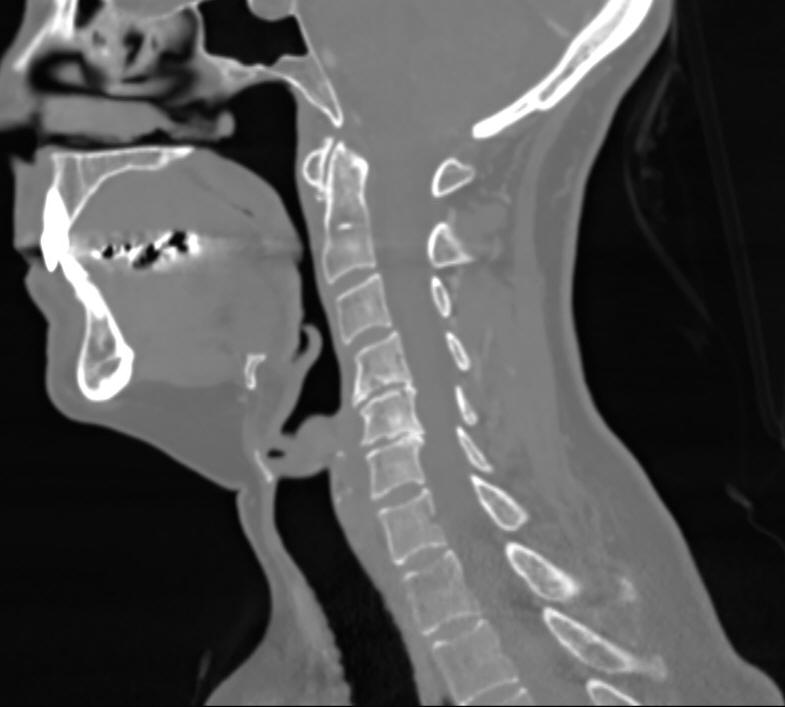

CT Scanning - Neck

A neck CT checks the soft tissues of the neck and is frequently used to study a lump or mass in the neck or to look for enlarged lymph nodes or glands.